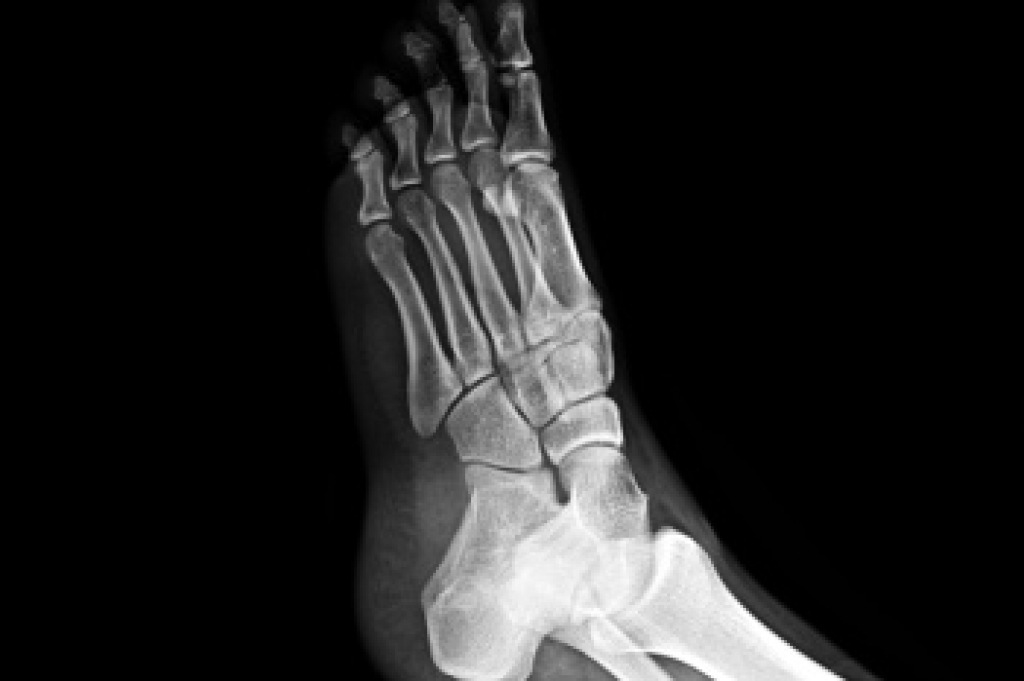

Metatarsal bone fractures occur when one of the long bones in the middle of the foot breaks, often from trauma, overuse, or a sudden twist. These fractures can be open, where the bone pierces the skin, or closed, where the skin remains intact. They may also be displaced, meaning the bone pieces are out of alignment, or nondisplaced, where the bone remains properly aligned. A podiatrist can assess the injury through examination and imaging, provide proper immobilization, and recommend treatment to promote healing and prevent long-term complications. Early diagnosis is vital to restoring foot function and mobility. If you have foot pain or feel you may have broken a bone, it is suggested that you promptly visit a podiatrist who can accurately diagnose and treat what is going on.

A broken foot is caused by one of the bones in the foot typically breaking when bended, crushed, or stretched beyond its natural capabilities. Usually the location of the fracture indicates how the break occurred, whether it was through an object, fall, or any other type of injury.